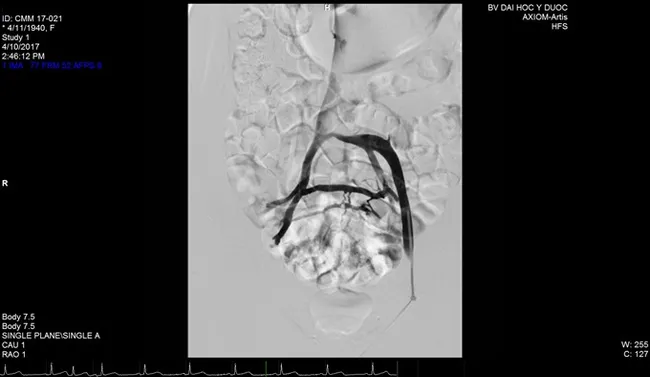

A radiograph image of a patient with May-Thurner syndrome shows an overlying right common iliac artery compressing and obstructing the left common iliac vein. — Photo courtesy of the HCM City University Medical Centre

The syndrome, also known as iliac vein compression syndrome and Cockett’s syndrome, is caused by an anatomical anomaly in which the left common iliac vein is compressed by the overlying right common iliac artery.